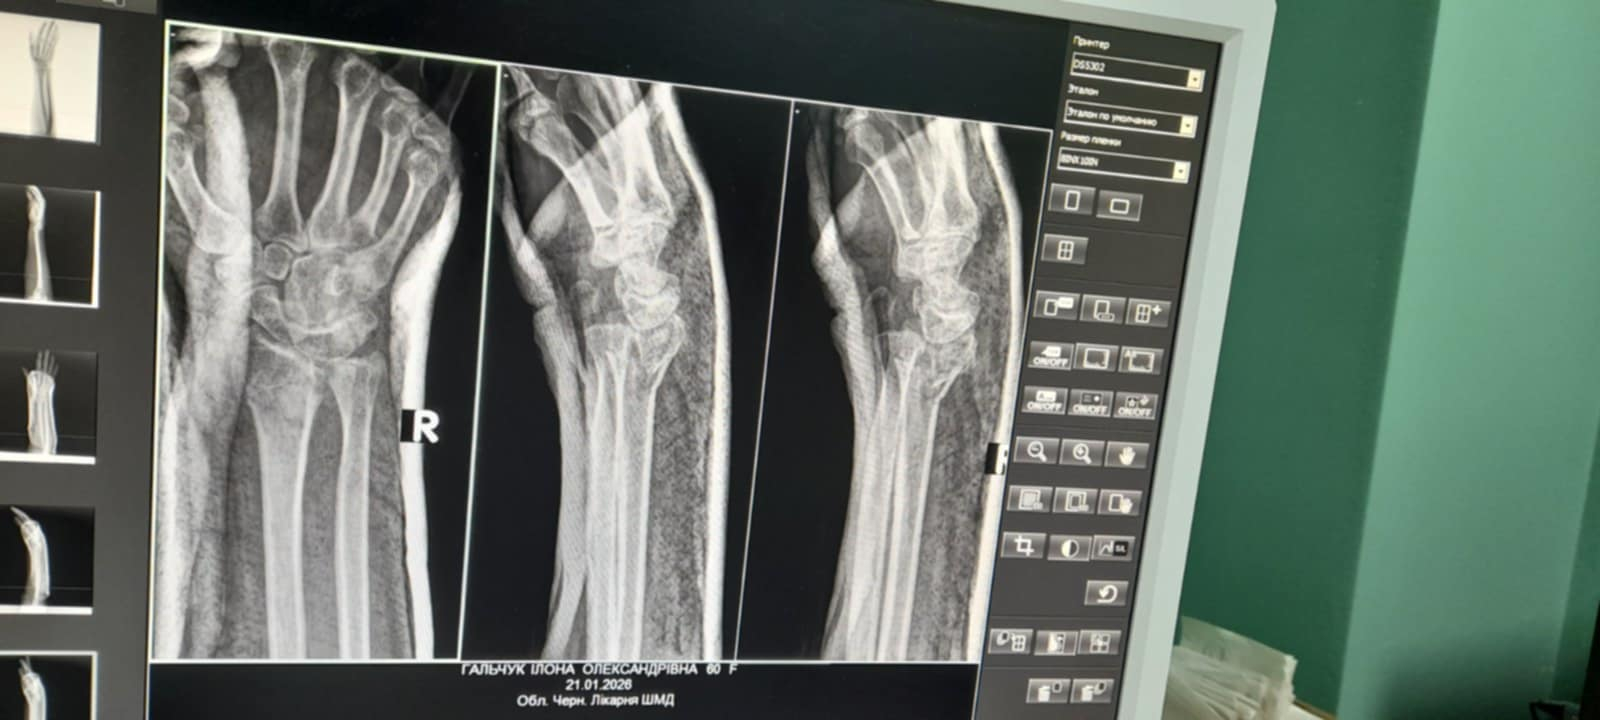

Перелом зростався погано. Довелося робити операцію – до кісток прикрутили металеву пластину. Операція коштувала 23 700 гривень. "Тільки за залізячку", – уточнює Ілона. При пенсії 3700.